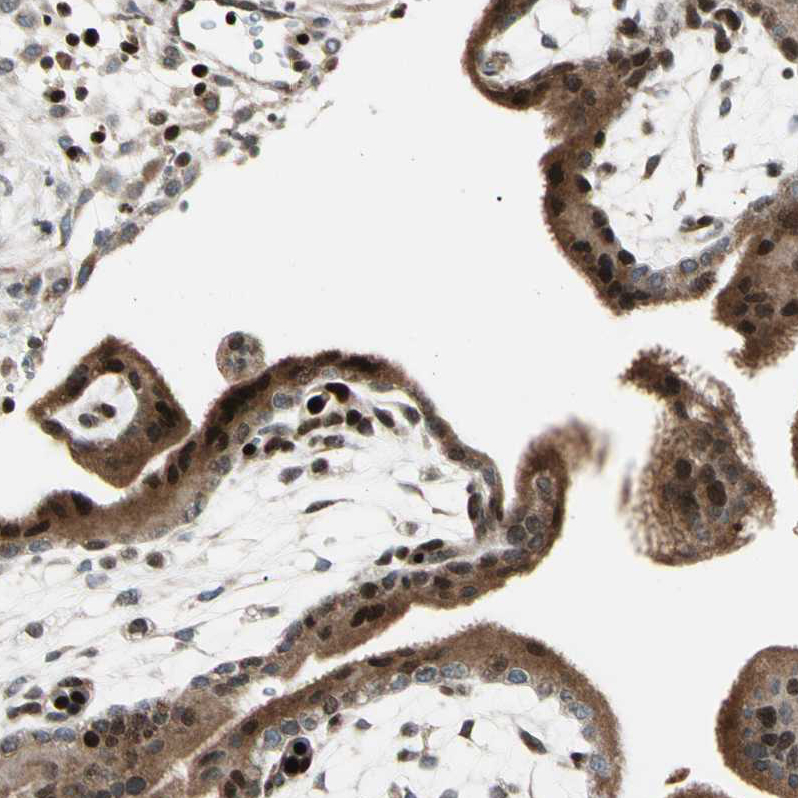

Immunohistochemical staining of human skin shows moderate to strong nuclear positivity in keratinocytes.